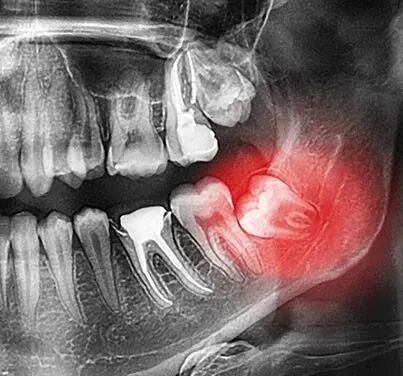

某女,36 岁,因左下智齿冠周炎反复发作在某医院口腔科就诊,经拍片,初步诊断为左下颌第三磨牙近中水平阻生,行智齿拔除术。

据术前X线片,当地医学会和本次事故鉴定专家均认为本病例为下颌第三磨牙的“水平阻生”,而医生的原诊断是“近中水平阻生”。

细微的误差、概念的模糊,使其对拔牙阻力的分析产生错误。一般说来,水平阻生牙的阻力既有邻牙的阻力,还有颊侧、远中或舌侧牙槽骨处的阻力。

有经验的术者多要做下颌第2磨牙颊侧的龈切口、翻开龈瓣,适当凿去牙槽骨;充分显露阻生牙,采用适宜的方式劈冠,以解除所有各个方向上的阻力;最后从阻力最小的方向挺出牙齿。

所以,拔除此类阻生牙的难度较大,手术时间多较长。如果操作正确,出现完全性骨折并不多见。